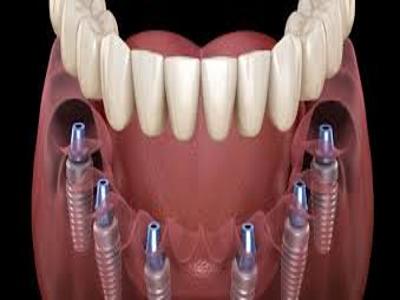

Elevate your dental care journey with our membership program, specifically designed for patients seeking teeth implants. As a member, you’ll benefit from reduced pricing on implant procedures, priority scheduling for consultations and treatments, and continuous follow-up care to ensure the best outcomes. Join today to access top-tier dental implant services and enhance your smile with confidence.